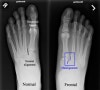

양측 체중부하 상태, 체중부하하지 않은 상태에서 족부 정면 X-ray 사진을 찍습니다.

제 1, 2 중족골 기저부의 간격이 건측에 비해 크고 체중부하 상태에서의 해당 간극의 변화가 건측에 비해 큽니다.

내측, 중간 설상골 사이가 벌어져 있으며, 설상골간인대도 파열되어 있습니다.

X-ray : Lisfranc 인대 손상 (Lisfranc injury, Midfoot sprain)